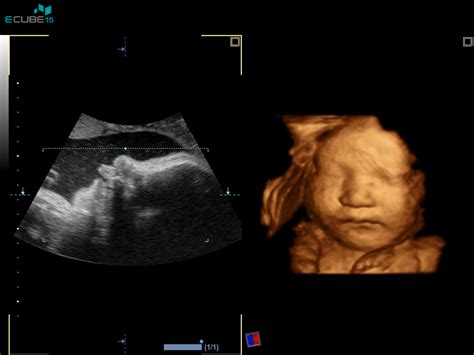

- 3D/4D ultrazvočni pregled ploda: Omogoča staršem vpogled v videz in gibanje njihovega malčka, kar lahko krepi čustveno povezavo.

Morfologija ploda, ki se običajno opravi med 20. in 22. tednom nosečnosti, je temeljit ultrazvočni pregled, namenjen oceni plodove rasti in razvoja. Z meritvami glavice, trebuščka in stegnenice se oceni gestacijska starost in rast. Sledi natančen pregled vseh ključnih organov in organskih sistemov, vključno s srčkom, ki mu je posvečena posebna pozornost. Pregledajo se tudi hrbtenica, okončine ter položaj ploda v maternici, posteljica, popkovnica in količina plodovnice. V večini primerov je mogoče ugotoviti tudi plodov spol, vendar se ta razkrije le na željo staršev. Če se med ultrazvočno preiskavo odkrijejo nepravilnosti, nosečnico o tem obvestijo in jo napotijo na nadaljnje preiskave. Kljub natančnosti te preiskave, je pomembno vedeti, da vseh razvojnih nepravilnosti, zlasti tistih, ki se razvijejo kasneje ali po rojstvu, ne moremo izključiti.